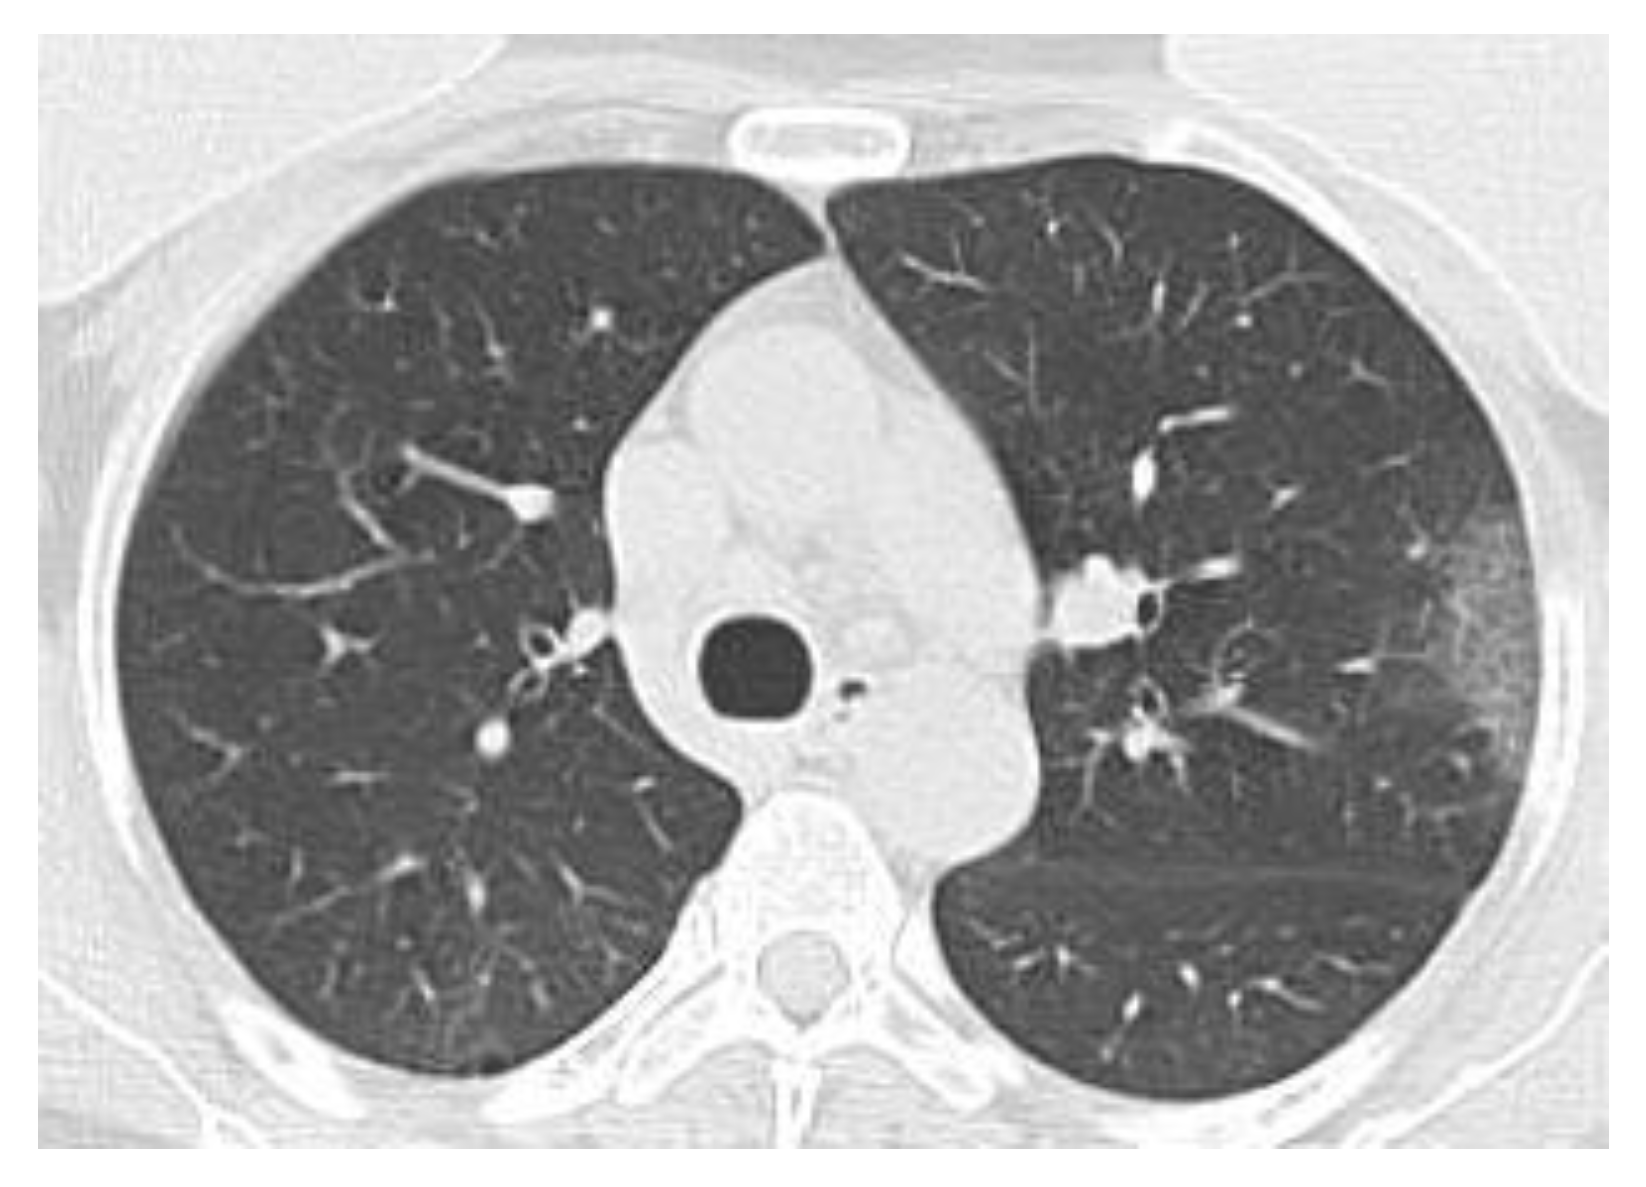

Figure 17 and Figure 18 show the original non-COVID-19 CT pulmonary picture, respectively, and the defined mask for the non-COVID-19 CT pulmonary picture, framed in a blue border, Figure 18.

Figure 17. Original non-COVID-19 lung image.